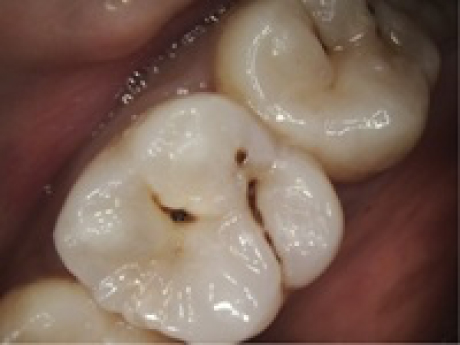

case2